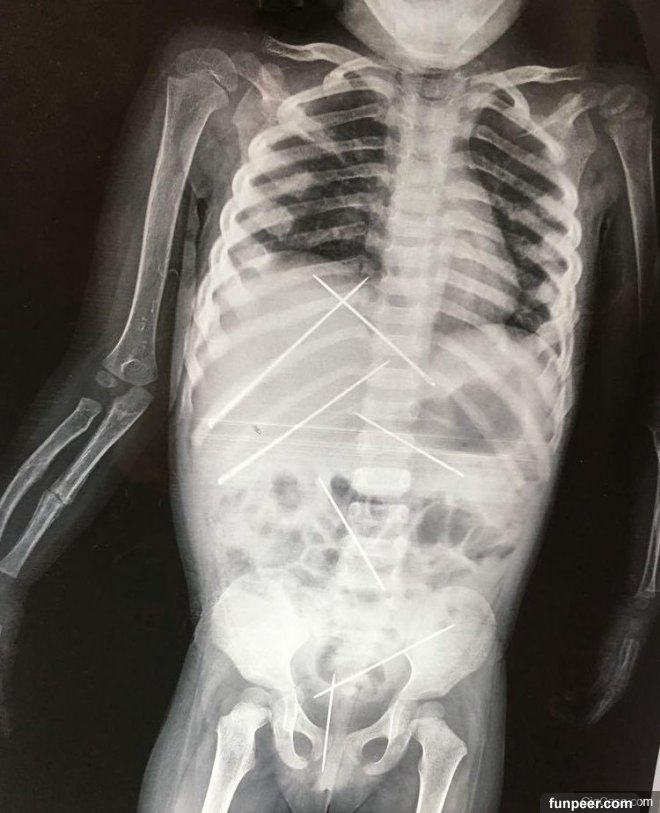

▲女童體內竟然......(source: thesun,以下同)   大家好我是雲編~ 今天要跟大家分享一則可怕的消息。小孩是非常脆弱的,特別是還不太會講話的小孩,特別需要爸媽來保護他們的安危。可是當爸媽失職或沒有能力保護孩子的時候該怎麼辦?根據thesun報導,最近印度就發生了一起相當驚人的事件,一名母親將年僅3歲的女兒帶到加爾各答的SSKM醫院,醫生幫小女孩照了X光後,全都嚇壞了......   ▼小女孩的腹部竟然有好幾根長達5公分的針,手臂也斷了。   媽媽說那些針大概已經扎進去15-20天了......她表示她被一名年老的男人僱用當傭人,女兒是被僱主虐待,推測是因此斷手之後,媽媽才抱着女兒來醫院。   ▼媽媽抱着女兒Supriya Goswami。   一開始因為女童狀況不太好,醫院沒有立刻取出針,所幸後來女童狀況比較穩定,也順利將針取出。 目前警方也已經將僱主逮捕,據調查,他似乎還在施行「黑魔法」,不確定在女童身上扎針是否也是黑魔法的行為......   ▼女童體內取出的針。   真的滿可怕的......這個媽媽不知道是不是礙於僱主的淫威,所以沒有立刻帶女童到醫院。幸好後來女童有被治好,不然這個媽媽應該也會後悔一輩子!至於可惡的僱主......希望他可以受到該有的刑罰!   猜你可能也會想看... 7個「最讓人覺得性感的女生刺青部位」。#3最低調氣質、#5從上蔓延到下的誘惑! 3個「社會大學讀到10階滿等」才能看懂的「成人內涵笑話」。能看懂#3的絕對是「菁英中的菁英」! 小夫妻決定改造廚房「拆掉整片牆壁」,卻在裏面發現「詭異的結塊」,一個個挖出來之後忍不住「尖叫到崩潰」   文章來源:thesun,編輯整理